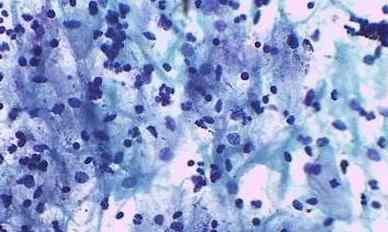

巴氏涂片检查

可发现早期子宫颈癌症状,及早发现,治愈率更高。建议从21岁开始每年查一次。到30岁时,如果连续3次检查结果正常,65岁前可以每3年查一次。